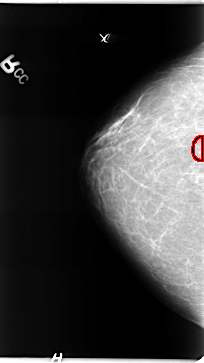

B_3136_1.RIGHT_MLO

B_3136_1.RIGHT_CC

FILE: B_3136_1.RIGHT_CC.OVERLAY

TOTAL_ABNORMALITIES 1

ABNORMALITY 1

LESION_TYPE CALCIFICATION TYPE PLEOMORPHIC DISTRIBUTION CLUSTERED

ASSESSMENT 4

SUBTLETY 4

PATHOLOGY MALIGNANT

TOTAL_OUTLINES 1

BOUNDARY